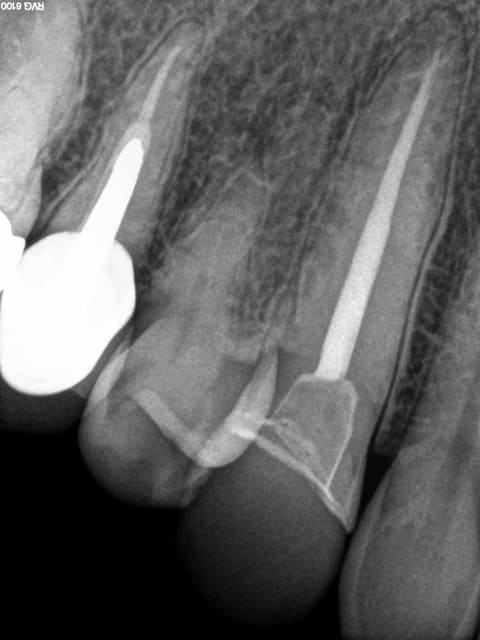

Endo couronne cerec sur 13, 8 ans après.